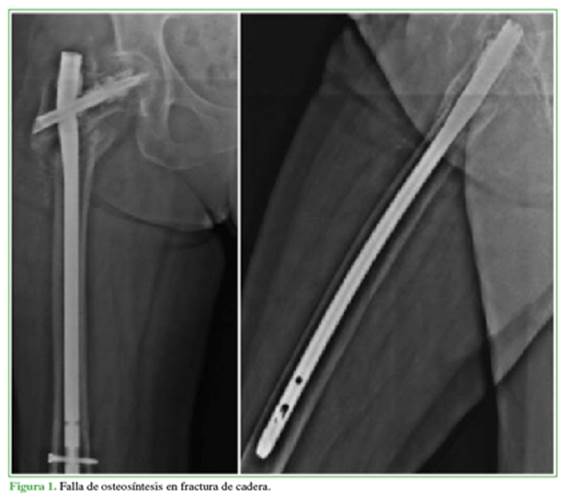

Se presenta el caso de una mujer de 66 años, con antecedentes de alcoholismo, HTA y osteosíntesis fallida con clavo céfalo-medular por fractura intertrocantérica de cadera derecha (AO 31-A3.1), realizada en 2017 (Figura 1).